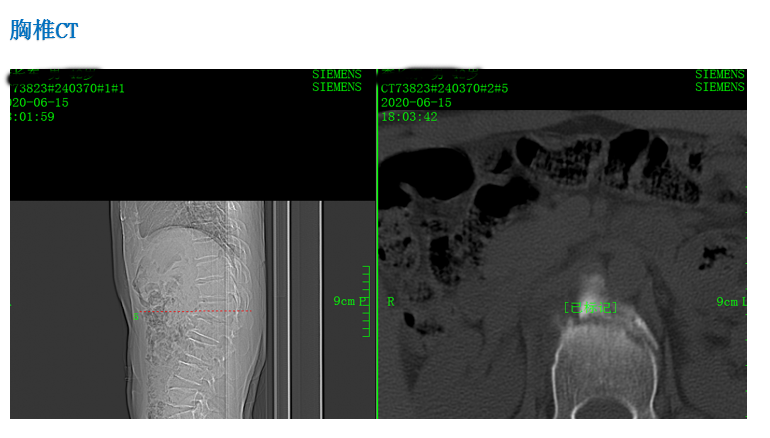

患 者:李某,男,42岁。

主 诉:因摔伤致腰背部、右跟部疼痛伴活动受限2小时,入院治疗。

症 见:患者从2米高处摔下,双足着地,即觉腰背部、右跟部疼痛伴活动受限,受伤当时无胸闷气促,无恶心呕吐。

专科检查:胸腰椎稍后突,胸腰部稍肿胀,无瘀青,皮肤黏膜完整,腰1、2棘突处轻压痛,腰2椎旁轻压痛,局部叩痛,双侧沿坐骨神经区无压痛,右大腿前中部感觉减退。双大腿内侧、内踝、第3跖趾关节背侧、足跟外侧感觉无减退。肛门反射存在,双侧膝反射、双侧踝反射消失。髂腰肌肌力(Ⅴ级)。双侧股四头肌肌力(Ⅴ级),双侧胫骨前肌肌力(Ⅴ级),双侧踇长伸肌肌力(Ⅴ级),双侧踇长屈肌肌力(Ⅴ级),双侧踝关节跖屈(小腿三头肌)肌力(Ⅴ级)。直腿抬高试验(-)、加强试验(-),拾物试验(不能配合完成)。腹壁反射、肛门反射正常。右肾区叩击痛(+),左肾区叩击痛(-),输尿管移行区无叩击痛。左髋部叩击痛,髋关节活动可,4字征(-)。右外踝、跟部肿胀,皮肤黏膜完整,局部可见皮下淤血,压痛,未触及骨擦感,足背动脉可及,右足末梢感觉无减退,右踝外侧应力试验、抽屉试验不能配合,右踝关节主动活动稍受限,右足各趾活动可。

影像资料:

诊 断:

1:腰1、2椎体压缩骨折(椎体分别压缩约40%、10%);

2:腰椎退行性改变伴椎管狭窄;

3:腰3/4、4/5、腰5/骶1椎间盘膨出;

4:右跟骨骨折;

5:胸12陈旧性骨折。